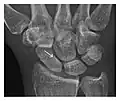

Figure 3: A 26-year-old man presenting with wrist pain after being assaulted. (a) Initial anteroposterior radiograph shows a subtle linear lucency within the scaphoid extending to the scaphocapitate articular surface that was overlooked (arrow). (b) Initial "scaphoid" view was negative. (c) Followup anteroposterior radiographs, 12 days later, shows obvious scaphoid fracture (arrows).[1]

Triquetral fracture usually occurs on the dorsal aspect by impingement from the ulnar styloid or avulsion of strong ligamentous attachment. The dorsal avulsion fracture or "chip fracture" appears as a small bony fragment on the dorsal aspect of the triquetrum and is best detected on the lateral view(Figure 4). When radiography is negative in patients with high suspicion of a fracture, both MRI and MDCT will be of value. However, it has been shown that MRI is superior for detecting trabecular fractures in carpal bones.